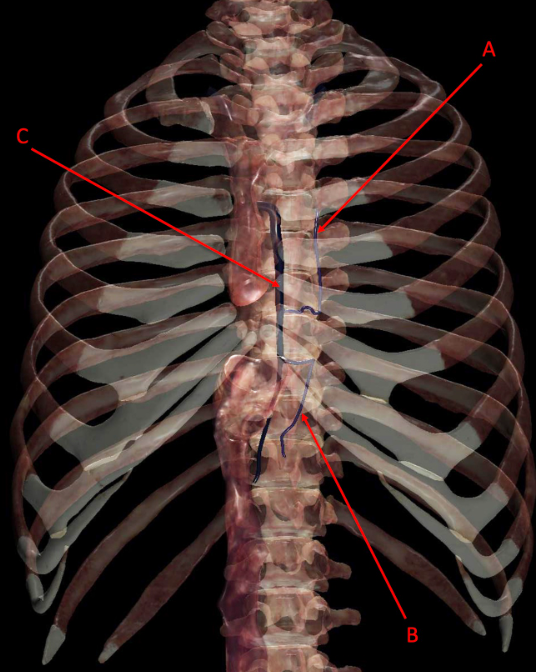

Q

Identify the following structure(s)

A

A. accessory hemiazygous vein

B. hemiazygous vein

c. azygous vein